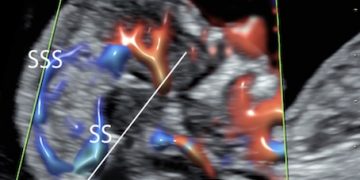

How To Do Settembre 2022: corretto settaggio del Doppler in ostetricia

Cari soci, questo mese un nuovo video "How to do", sul corretto settaggio del Doppler in Ostetricia. Grazie a Paola Quaresima! Il video è accessibile ai soli soci SIEOG attraverso...